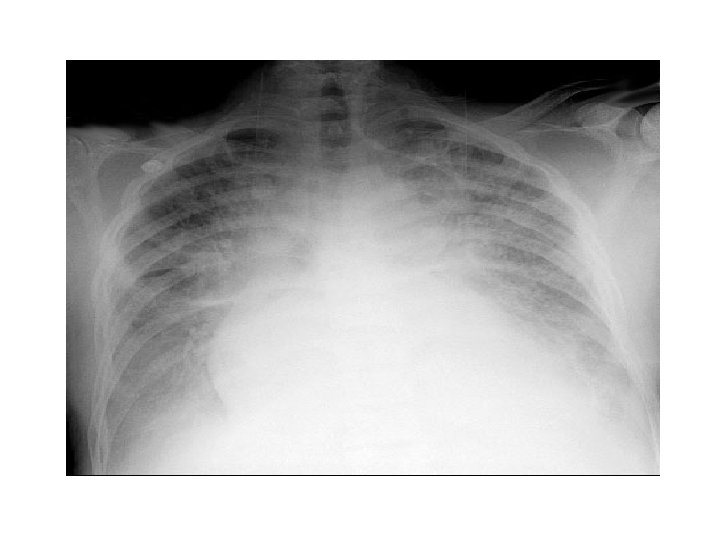

Congestive Cardiac Failure • • • Alveolar oedema Kelly B lines Cardiomegally Upper lobe deviation Pleural Effusion